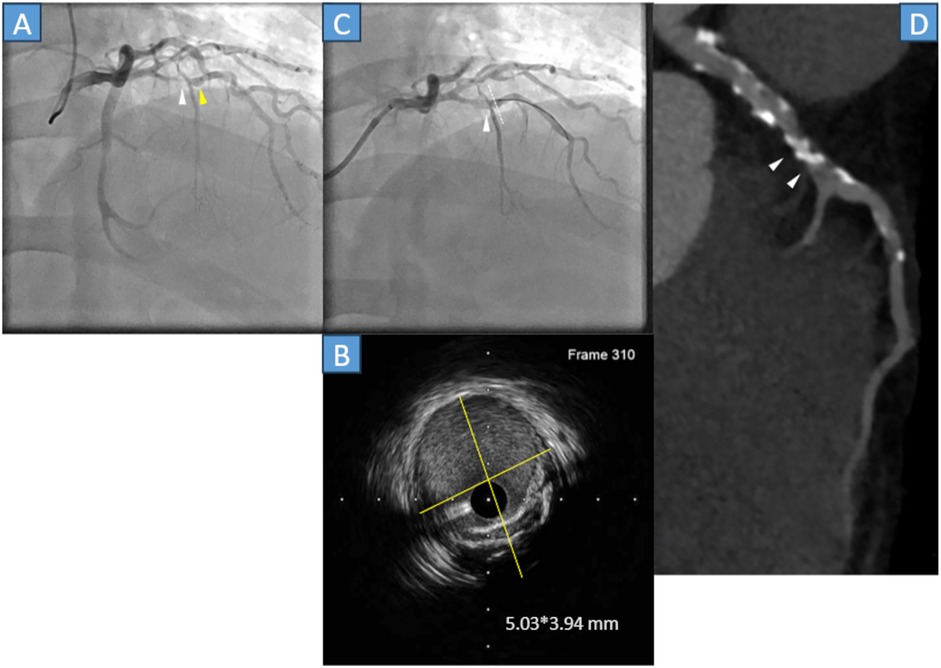

A 49-year-old male with a history of stent-assisted coiling of an intracranial aneurysm, hypertension, and dyslipidemia without Kawasaki disease was admitted to our hospital because of chest pain. The ECG did not show any substantial changes; however, the cardiac troponin T level was 0.083 ng/mL (normal range, <0.014 ng/mL). Emergency CAG was performed because of a non-STEMI. The CAG demonstrated that the proximal LAD artery had severe stenosis (Figure 3A, white arrowhead) with an aneurysm (Figure 3A, yellow arrowhead). Thus, in April 2022, PCI was performed. A 0.014-inch guidewire was crossed, and IVUS was performed. IVUS revealed a 5.03*3.94 mm aneurysm and lesion calcification (Figure 3B yellow lines, Figure 3C white dots). After dilating the lesion with a 2.5*13 mm scoring balloon, a 3.0*15 mm paclitaxel DCB was used; final CAG showed a fusiform coronary aneurysm, whose flow with National Heart, Lung, and Blood Institute grade A dissection (Figure 3C, white arrowhead). Following PCI, the patient was asymptomatic, and medication therapy: Aspirin, clopidogrel, statin, and ezetimibe. After 3 months, clopidogrel was discontinued. Approximately 3 years and 3 months later (July 2025), cardiac CT was performed. The LAD was calcified, and the target lesion was patent (Figure 3D, white arrowheads).

Figure 3

Panel A shows a coronary angiogram with plaques indicated by arrows. Panel B is an intravascular ultrasound image with measurements of 5.03 by 3.94 millimeters. Panel C shows a follow-up angiogram. Panel D displays a CT scan highlighting calcified plaques with arrows.

Figure 3. (A) Coronary angiography (CAG) showed stenosis just before the septal branch (white arrowhead) and aneurysm (yellow arrowhead). (B) The cross-sectional image of the intravascular ultrasound (IVUS) indicates a 5.03*3.94 mm aneurysm with calcification (yellow lines). (C) Final CAG reveals that the left anterior descending (LAD) artery was dilated with National Heart, Lung, and Blood Institute grade A dissection (white arrowhead). The white dots in the angiography correspond to the cross-sectional IVUS image. (D) Cardiac computed tomography indicates that the calcified lesion was patent (white arrowheads).